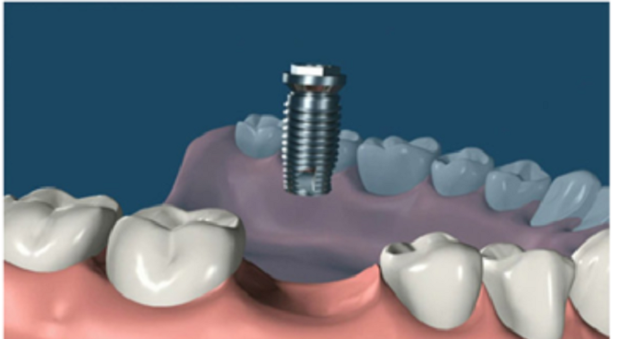

3. 植入種植體:這個(gè)時(shí)候開始進(jìn)行第一期手術(shù),手術(shù)將在牙槽骨上選擇合適的位置打洞,植入種植體后縫合創(chuàng)口,正常情況下整場手術(shù)時(shí)長在半個(gè)小時(shí)左右。